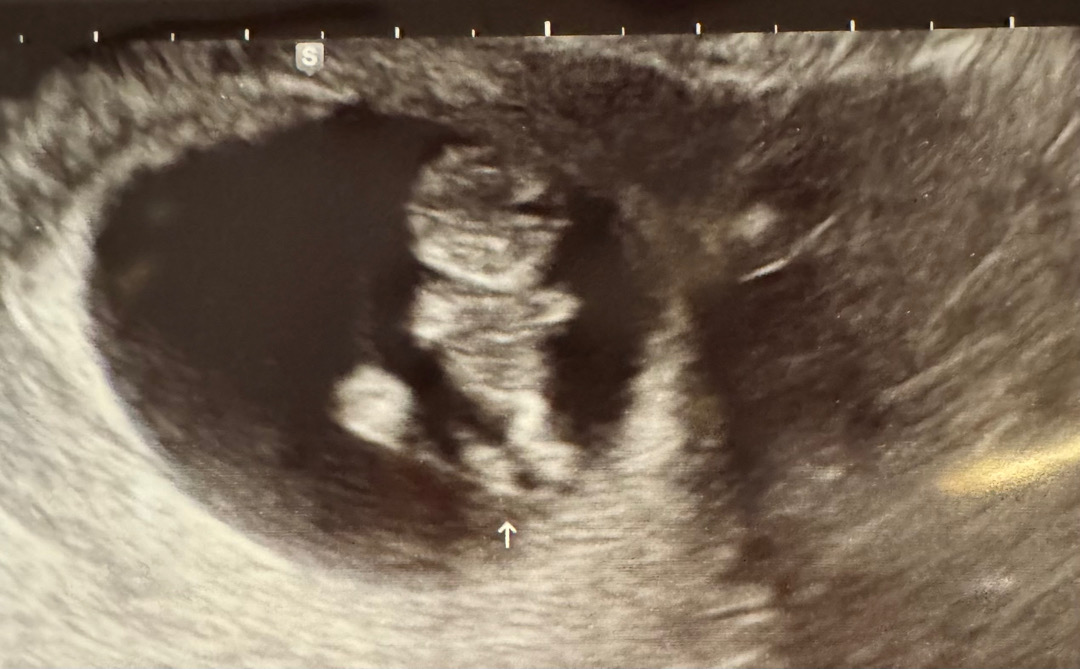

9주0일 초음파❤️

오늘 젤리곰 보고왓어요 ㅎㅎ 사람형태가 너무 신기했어요 :)